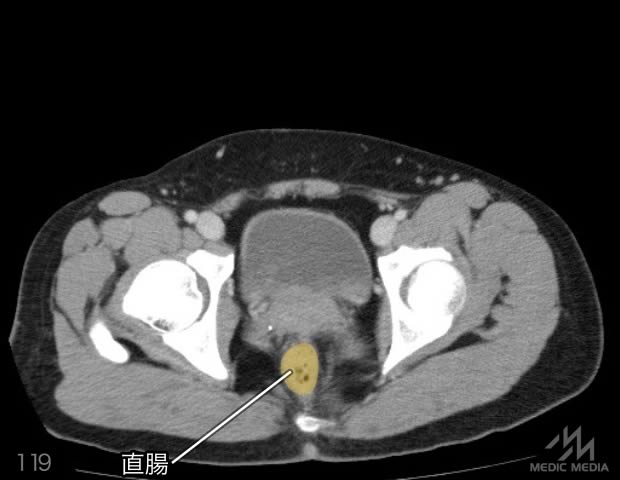

造影CT

スライド(画像下)を動かしながら,CTで臓器の位置を確認してみましょう.

消化器